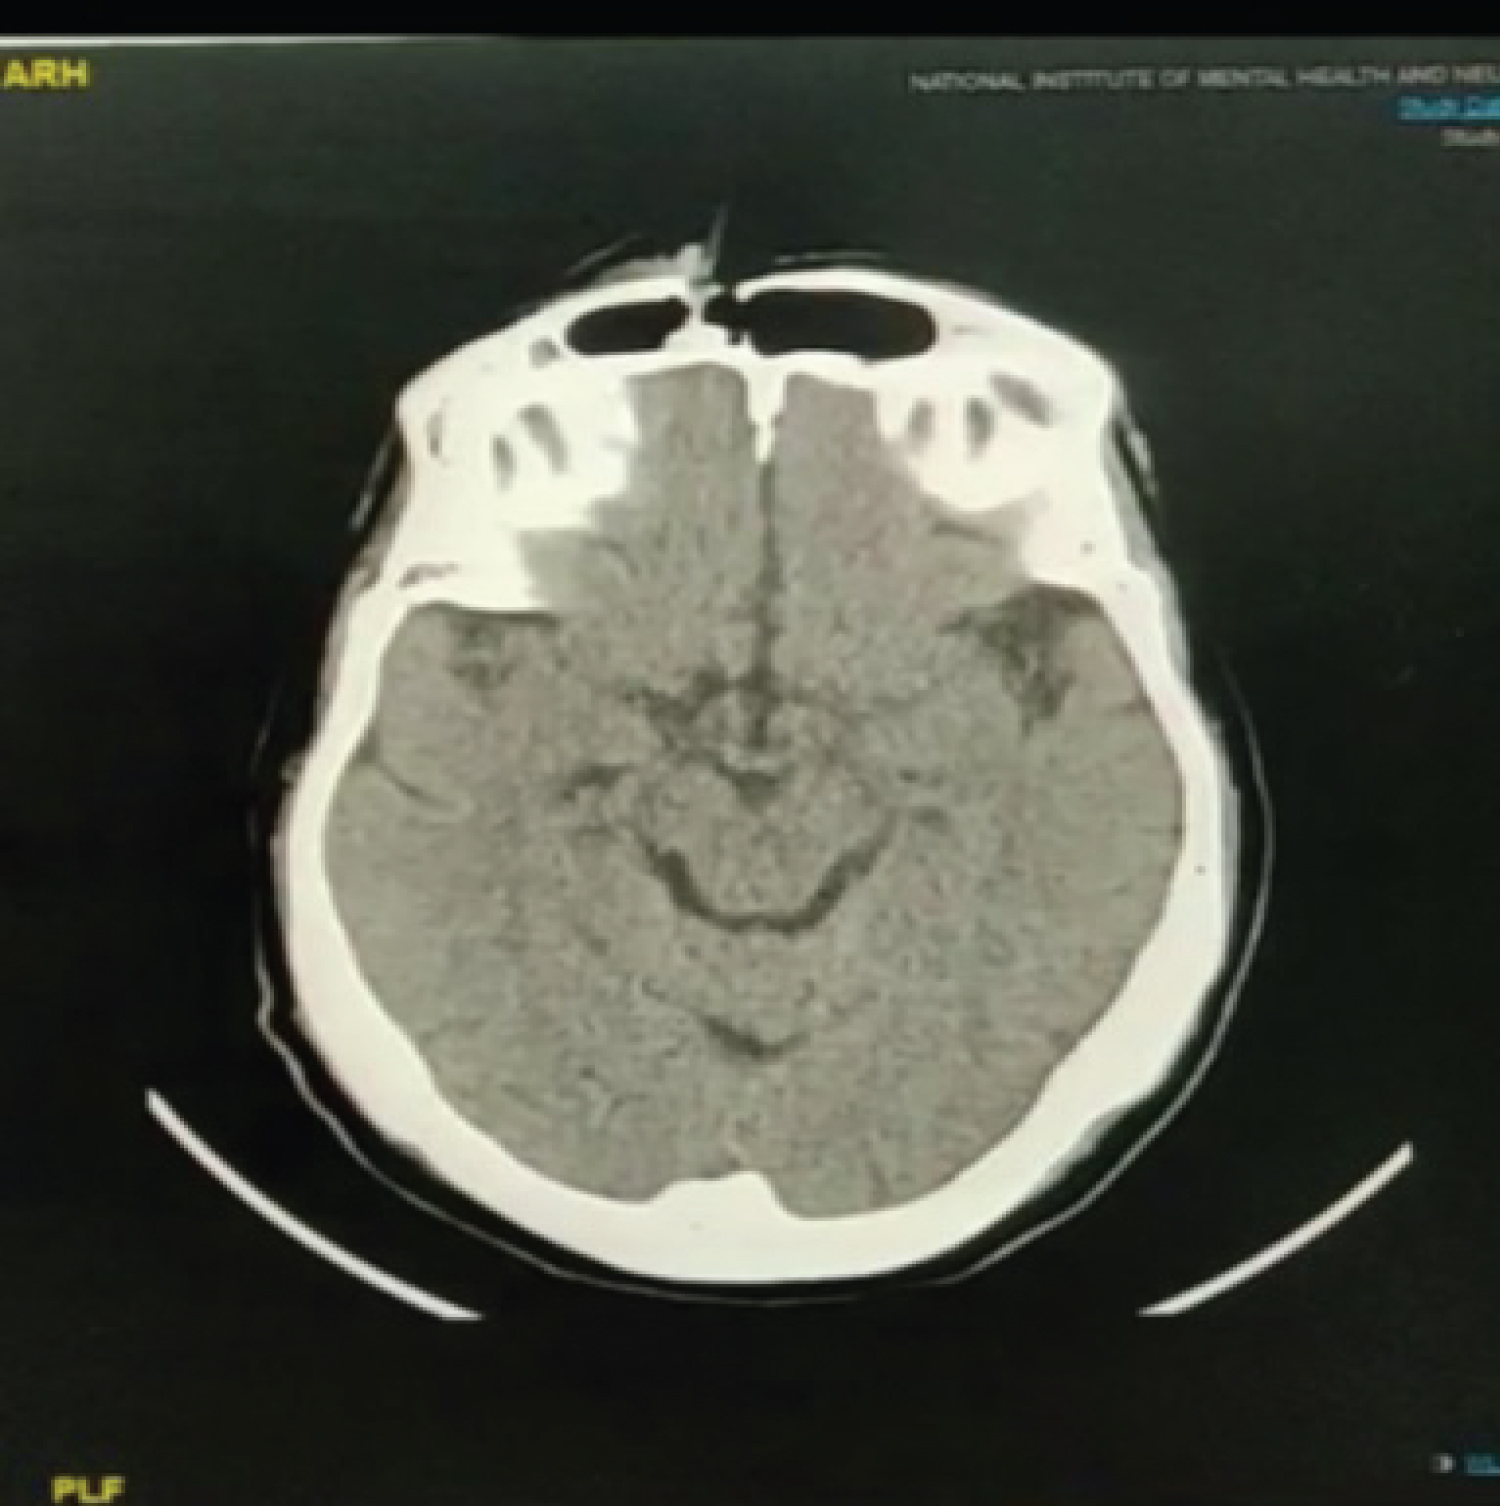

Following case report is noted as per CARE guideline. Proper consent has been taken from patient in her native language. A 72-years-old female admitted in SVP hospital in April, 2020 with complaint of forehead injury and brief episode of unconsciousness due to collision of bike with a tree, while she was a pillion rider. There were no signs and symptoms of raised intracranial pressure such as vomiting, difficulty in breathing and altered consciousness but there was history of unconsciousness and questionable convulsion which warrants neurosurgical attention. There was no leakage from nasal cavity as well as from both ears. She was having no co-morbidities and no previous operative history. She was conscious, oriented and co-operative at time of presentation. On neurological examination, her Glasgow coma scale was 15/15, cranial nerve examination was normal and no abnormalities were found in cerebellar examination. Power and tone were normal. There was no paresis, reflexes were normal. Sensory examination was normal. She was having no icterus, pallor, clubbing, cyanosis, edema and lymphadenopathy. On local examination there was a piece of wood which was piercing through her forehead just above medial end of left supraorbital ridge. Dimension of entry wound was approximately 3 × 3 cm size with oozing of blood at margins. There was slight edema surrounding it. There was no raccoon eye sign bilaterally. All routine investigations were done and were within normal limits. Ct brain was done. It was showing fracture of anterior table of left frontal sinus with presence of foreign body that had pierced through the wound. All pre-operative workup were done and the patient had giver consent after being informed of the risks of bleeding, infection, paresthesia, brain injury, CSF leak, meningitis, diplopia, visual loss, external deformity, and late mucocele formation. Then patient is shifted to operative room. Coronal flap is used and the full pericranial exposure was maintained. After full exposure foreign body carefully removed and thorough examination at local site was done. Fragments of anterior table were carefully removed and kept moist. Mucosa of frontal sinus is denuded from posterior table and cavity is examined for any CSF leak with concurrent Valsalva maneuver. Then cavity is cauterized and a small frontalis muscle plug is then placed into the frontal recess to obliterate the ostia. A fat graft is obtained through a left lower-quadrant (or periumbilical) incision using a separate, sterile instrument set. Fat graft was obtained in single attempt with minimal surrounding trauma. The fat graft was then trimmed and inserted into the sinus cavity to exclude the possibility of future development of CSF fistula. The anterior table fragments are replaced. Anterior table stabilization is achieved with micro plates, and bone plate described as "Open Reduction and Internal Fixation". Skin and soft tissue at local wound were approximated with non-absorbable suture material and sterile dressing applied. Coronal flap reposition carefully without development of tension in suture line. There was no post-operative leakage from wound or there was no nasal watery discharge. During post-operative period, patient's neurological examination was normal and there was no nasal discharge. She was treated with antibiotics, analgesics and anti-epileptics (it was for questionable convulsion that patient had after injury) during post-operative period. Patient was discharged on 3rd post-operative day. During follow up, suture were removed. There was no any sign and symptoms suggestive of CSF rhinorrhea and convulsion over 3 months of follow-up (Figure 1 and Figure 2).

Figure 2: Axial cut showing anterior table fracture. View Figure 2

Surgical treatment depends on wide exposure of the craniofacial skeleton via a bicoronal scalp flap or periorbital, intraoral, and extraoral incisions. Here involvement of only frontal sinus warrants bicoronal flap exposure. Line of treatment can be decided by assessing an anterior table fracture, a posterior table fracture, a nasofrontal recess fracture, a dural tear (CSF leak), and fracture displacement/comminution and as well as degree of displacement [7,8]. In this case there is only breach of anterior table that we can see in axial cut. There is little risk of morbidity with non-displaced anterior table fractures. Fractures having displacement of 2 to 6 mm present has risk of mucocele formation. Post-operative deformity chances increases with the degree of fracture displacement. An endoscopic repair may be possible if there is no wound over skin covering sinus site and posterior wall involved. Endoscopic treatment requires experience of surgeon and his expertise with endoscope [9]. This avoids the need for a coronal incision and also allows the patient to assess the degree of deformity after all facial edema has resolved. Patient gets two scars in this case, one over local trauma site and other of incision site. More complex anterior table fractures and those that extend below the orbital rim may require open reduction using a coronal incision. Obliteration of the frontal sinus with fat grafts through a frontal osteoplastic flap in patients with chronic sinusitis and mucocele formation has been applied by some to the treatment of frontal sinus fractures [10]. In this case we have done open reduction with internal fixation. Though there was unconsciousness and possibility of convulsion during post-traumatic phase, sudden hypotension following trauma or coupe injury might be the cause. Hence, we kept patient on levetiracetam during post-operative phase [11].